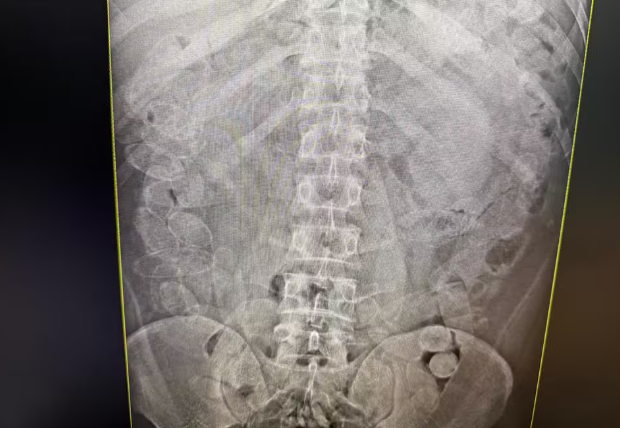

Diante da suspeita de que os demais homens pudessem ter ingerido a droga, os quatro foram encaminhados para um hospital da cidade, onde passaram por exames de raio X.

Um deles afirmou que não conseguiu engolir as cápsulas e que todo o material encontrado com ele era de sua responsabilidade. Já os outros três confessaram ter engolido cerca de 86 cápsulas cada um.